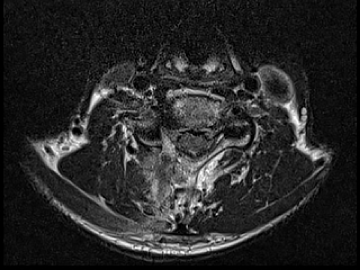

요추 협착증 수술 전·후

2022.08.08

2022.08.19

ㆍ환자 동의를 받은 자료이며, 이미지 사진은 실물과 다를 수 있습니다.

ㆍ모든 자료는 새움병원 자료입니다.